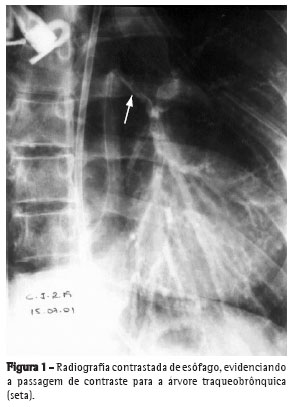

A radiografia de tórax de controle, após a endoscopia digestiva alta, revelou pneumotórax esquerdo. Foi realizada drenagem torácica esquerda com imediata reexpansão pulmonar. Na broncofibroscopia

observou-se área de destruição da traquéia distal, carina e brônquio esquerdo de aproximadamente 3 x 1,5 cm (Figuras 2 e 3), exposição de

tecido mediastinal, desepitelização e retração de epiglote e corda vocal direita.

O paciente apresentou evolução positiva, recebendo alta hospitalar dezessete dias após sua admissão. Dois meses após a alta, apresentava dispnéia progressiva nos últimos dez dias, tinha intensa

cornagem e tiragem intercostal. A broncofibroscopia mostrou uma estenose supraglótica (neoformação anular de tecido fibrótico) sendo indicada a traqueostomia. Foi mantido em acompanhamento